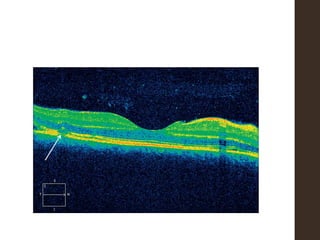

โ€ข Optical coherence tomography

ACUTE Stage โ€ข serousdetachment of the retina, โ€ข preservation of choriocapillaris from inflammatory cell infiltration, and โ€ข thickening of choroid from granulomatous inflammatory cell infiltration-

โ€ข No inflammationof the anterior segment or mild to moderate nongranulomatous anterior uveitis โ€ข Acute angle closure glaucoma(inflammatory infiltrate in the ciliary body and choroid may cause forward displacement of the lens iris diaphragm)-shallow AC, elevated IOP โ€ข Thickened choroid- B scan โ€ข FFA- Alteration in RPE associated with multifocal choroidal inflammation is easily observed by the hypofluorescence dots at the early phase followed by multiple focal areas of leakage and subretinal fluid accumulation at the late phase. โ€ข ICGA is useful to evaluate choroidal inflammatory changes such as early choroidal stromal vessel hyperfluorescence and leakage, and hypofluorescent dark dots at the level of the choroid.